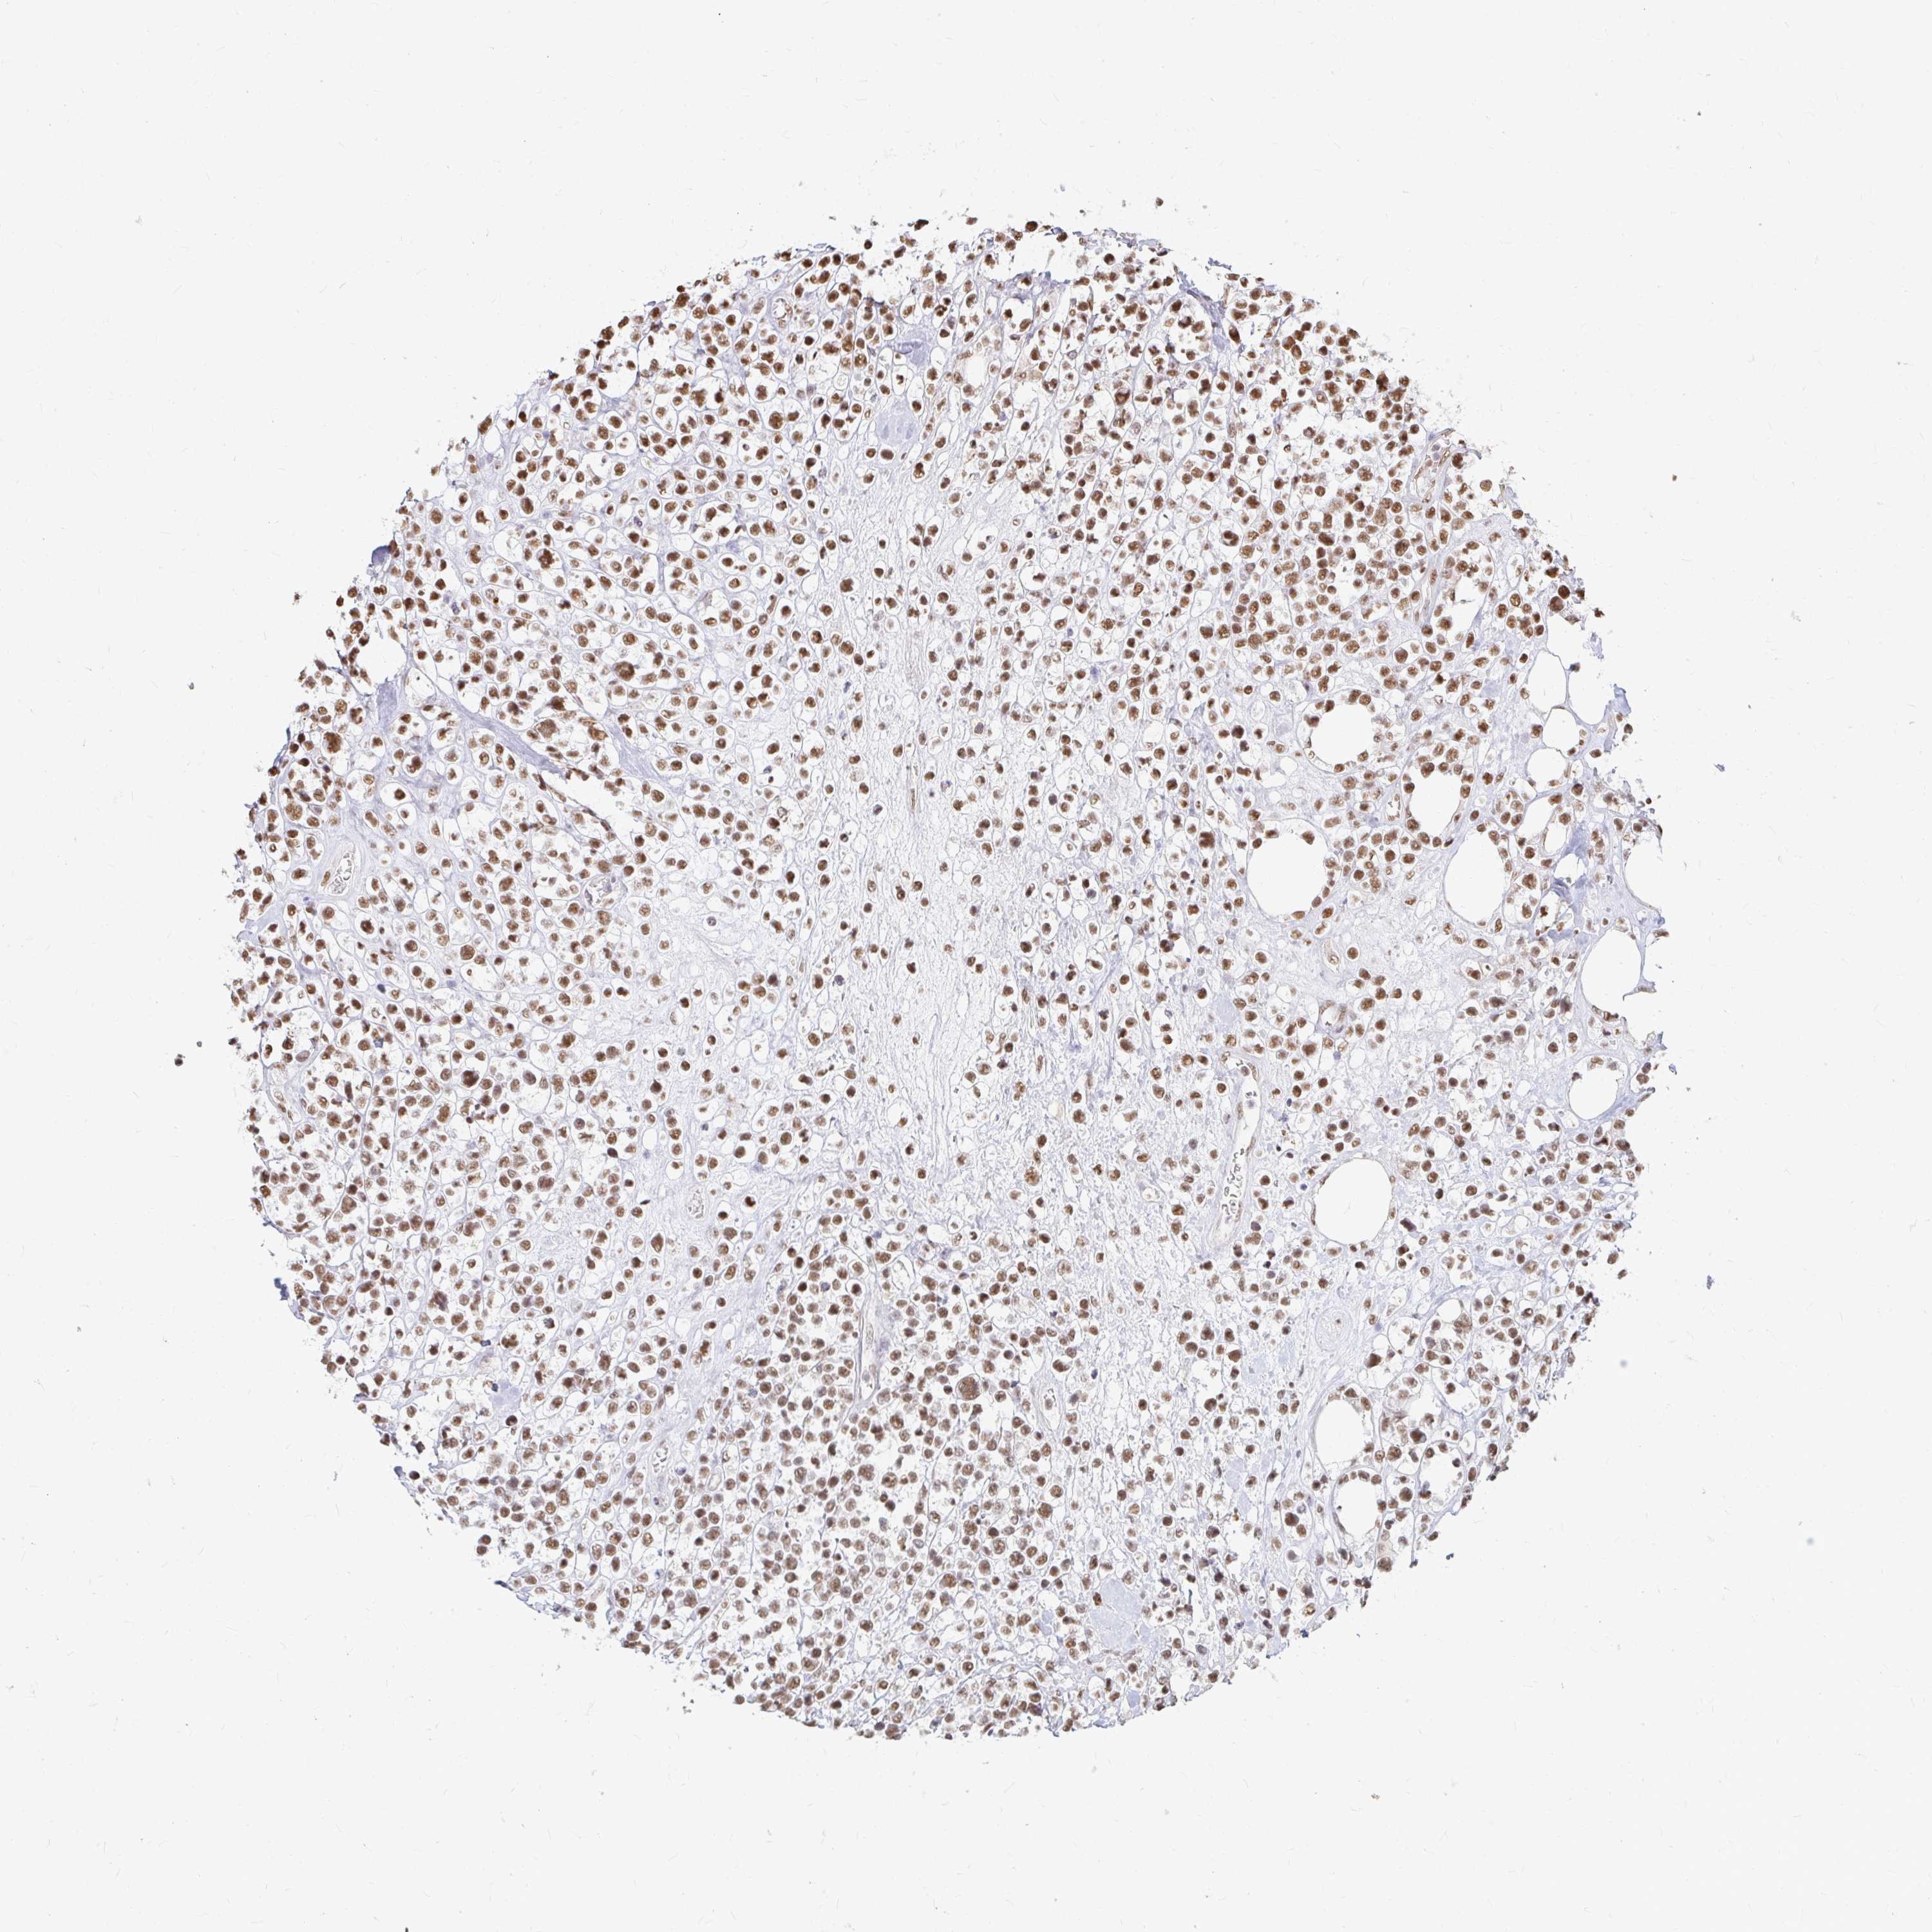

LYMPHOMA - Protein expressioni

A mouse-over function shows sample information and annotation data. Click on an image to view it in a full screen mode. Samples can be filtered based on level of antibody staining by selecting one or several of the following categories: high, medium, low and not detected. The assay and annotation is described here.

Each image is clickable and will lead to virtual microscopy that enables deeper exploration of all samples and also displays staining intensity scores, fraction scores and subcellular localization as well as patient and tissue information for each sample.

Antibody HPA041057

Staining

High

Medium

Low

Not detected

Intensity

Strong

Moderate

Weak

Negative

Quantity

>75%

75%-25%

<25%

None

Location

Nuclear

Cytoplasmic/membranous

Cytoplasmic/membranous,nuclear

Malignant lymphoma, non-Hodgkin's type, Low grade